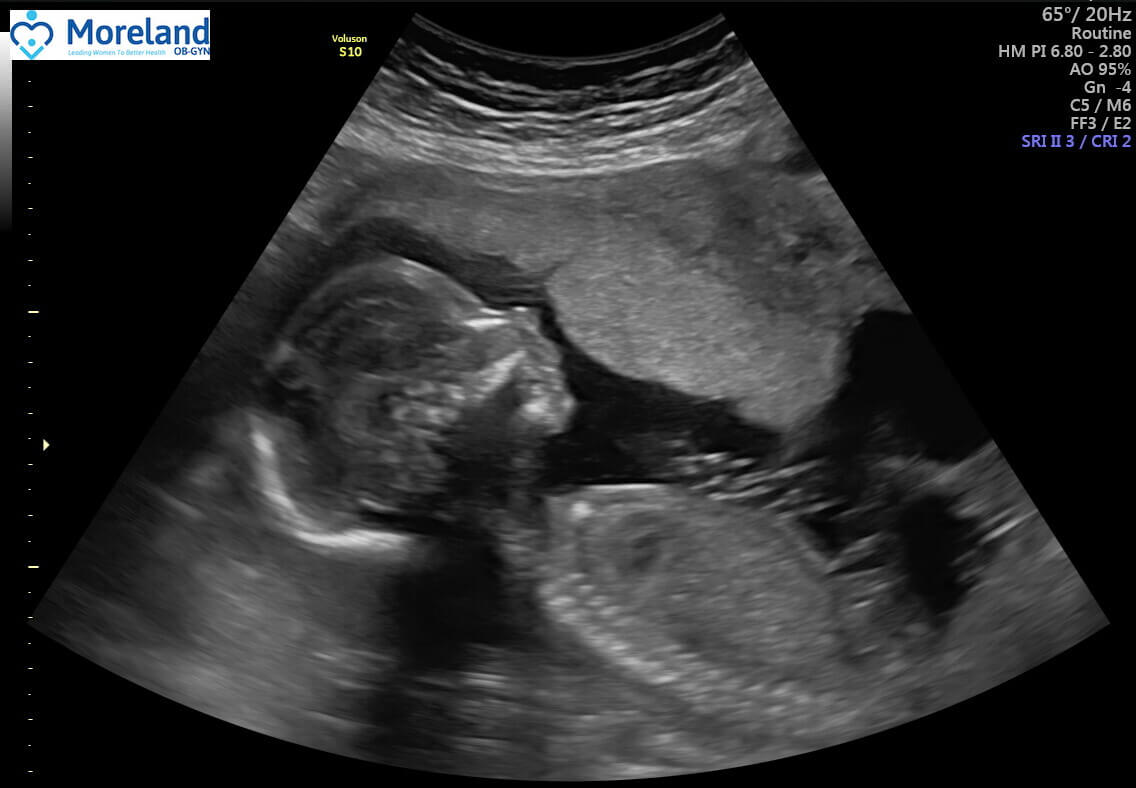

18-week ultrasound (size of a pint of ice cream)

He is still wiggling around SO much! Lots of stretches and thumb sucking. Everything looks great on the anatomy scan! He has daddy's nose!